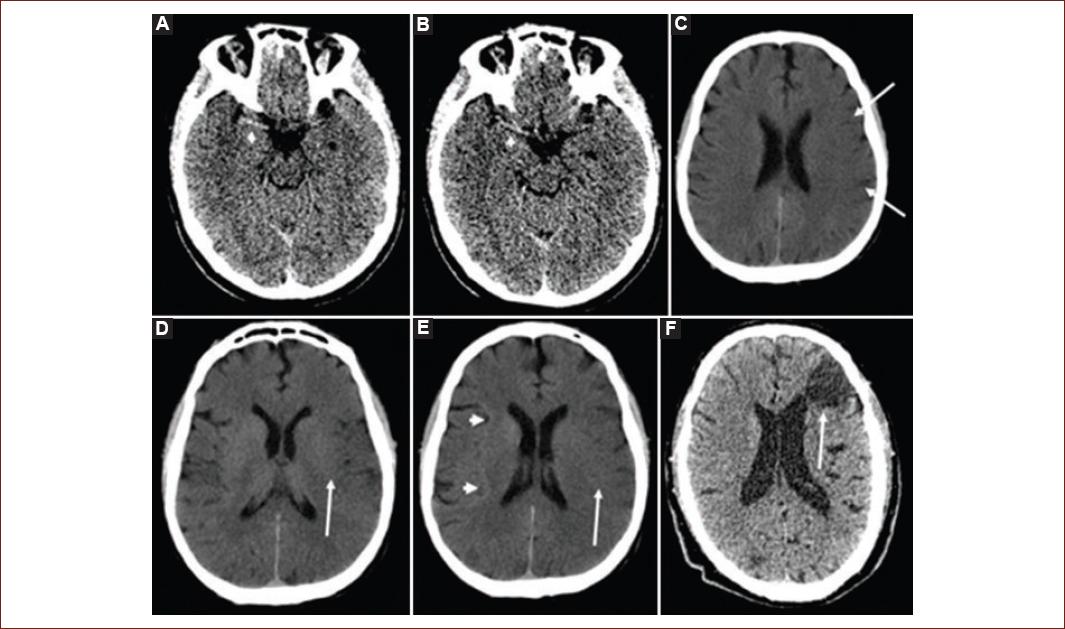

NCCT

Figure 1 Classic early ischemic signs in a non-contrast computed tomography: A and B: show a hyperdense right middle cerebral artery sign (white arrow head). C: shows the loss of gray-white matter differentiation at the surface cortex (white arrows). D: hypoattenuation of the lentiform nucleus (white arrow). E: loss of gray-white matter differentiation at the left insula (insular ribbon sign, white arrow) compared to a normal right insular ribbon (white arrowheads). F: shows a chronic cortical infarct (white arrow) with ventricular deforming due to gliosis.